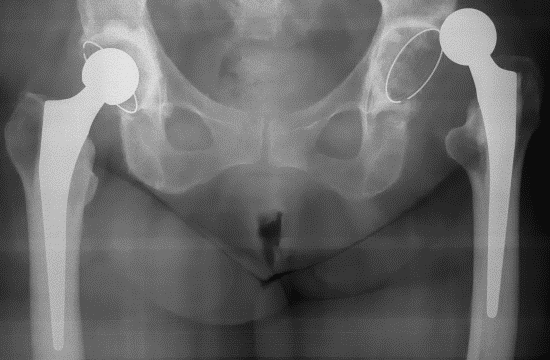

- Рентгеновские лучи. На фото хорошо видно расположение сустава и то, что он находится вне вертлужной впадины;